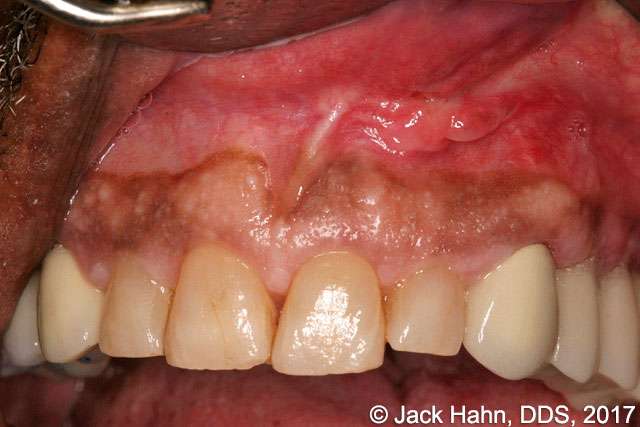

A patient presented to Jack Hahn, DDS, for a large swelling under the upper lip—a nasopalatine cyst (see Figure 1). Dr. Hahn opened the cyst with a scalpel, draining a substantial amount of exudate (see Figure 2). He then used his LightScalpel CO2 laser to sanitize the remaining cystic cavity, which also helped to manage the bleeding. He then sutured the cystic cavity shut (Figure 3). At six weeks post-operation the tissue is healing well (Figure 4).